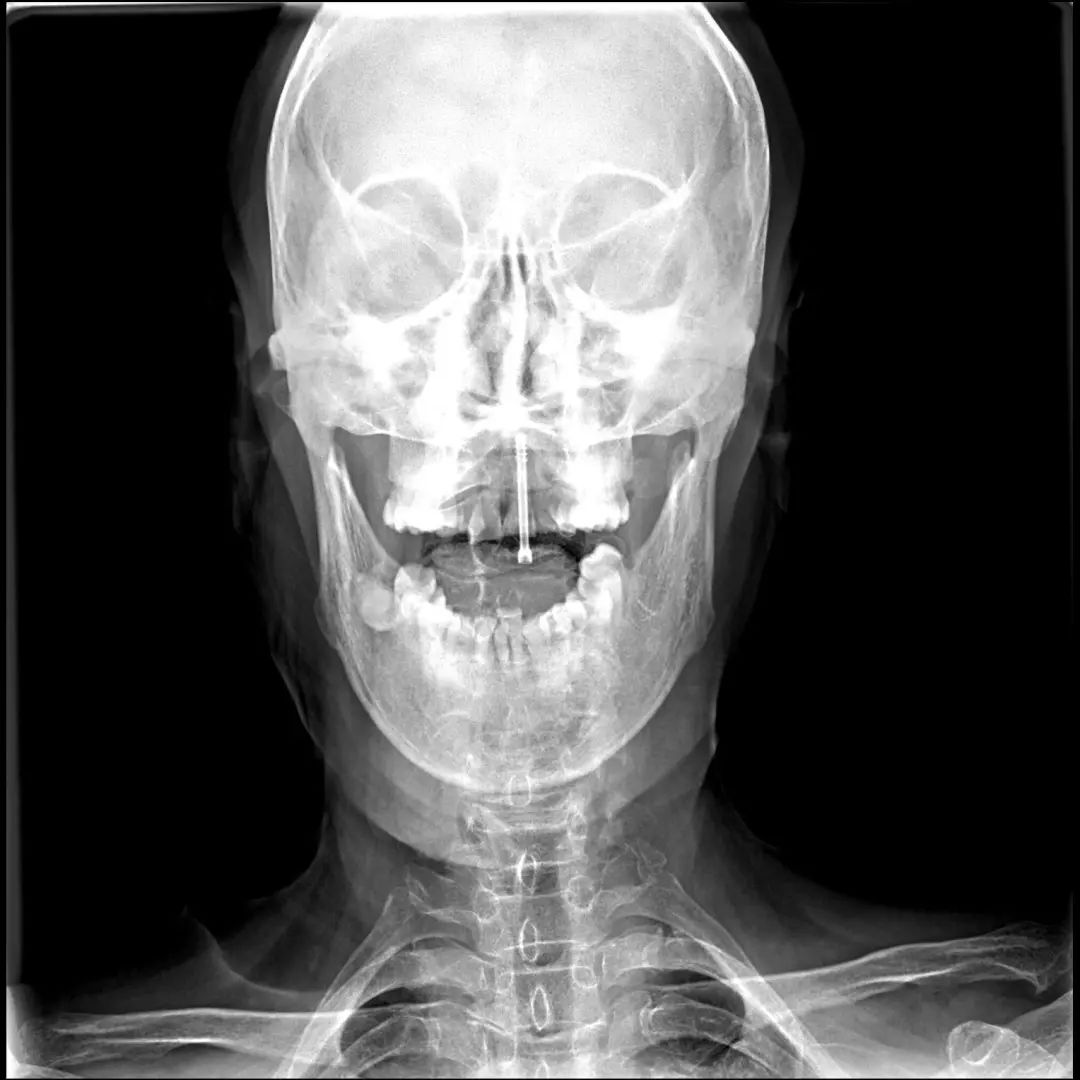

经过全程监护和系统治疗,患者术后恢复良好,骨折解剖复位,复查X线及CT显示固定位置佳,术后3天下地行走,术后4天即出院回家休养。

枢椎齿状突骨折后路Margerl手术